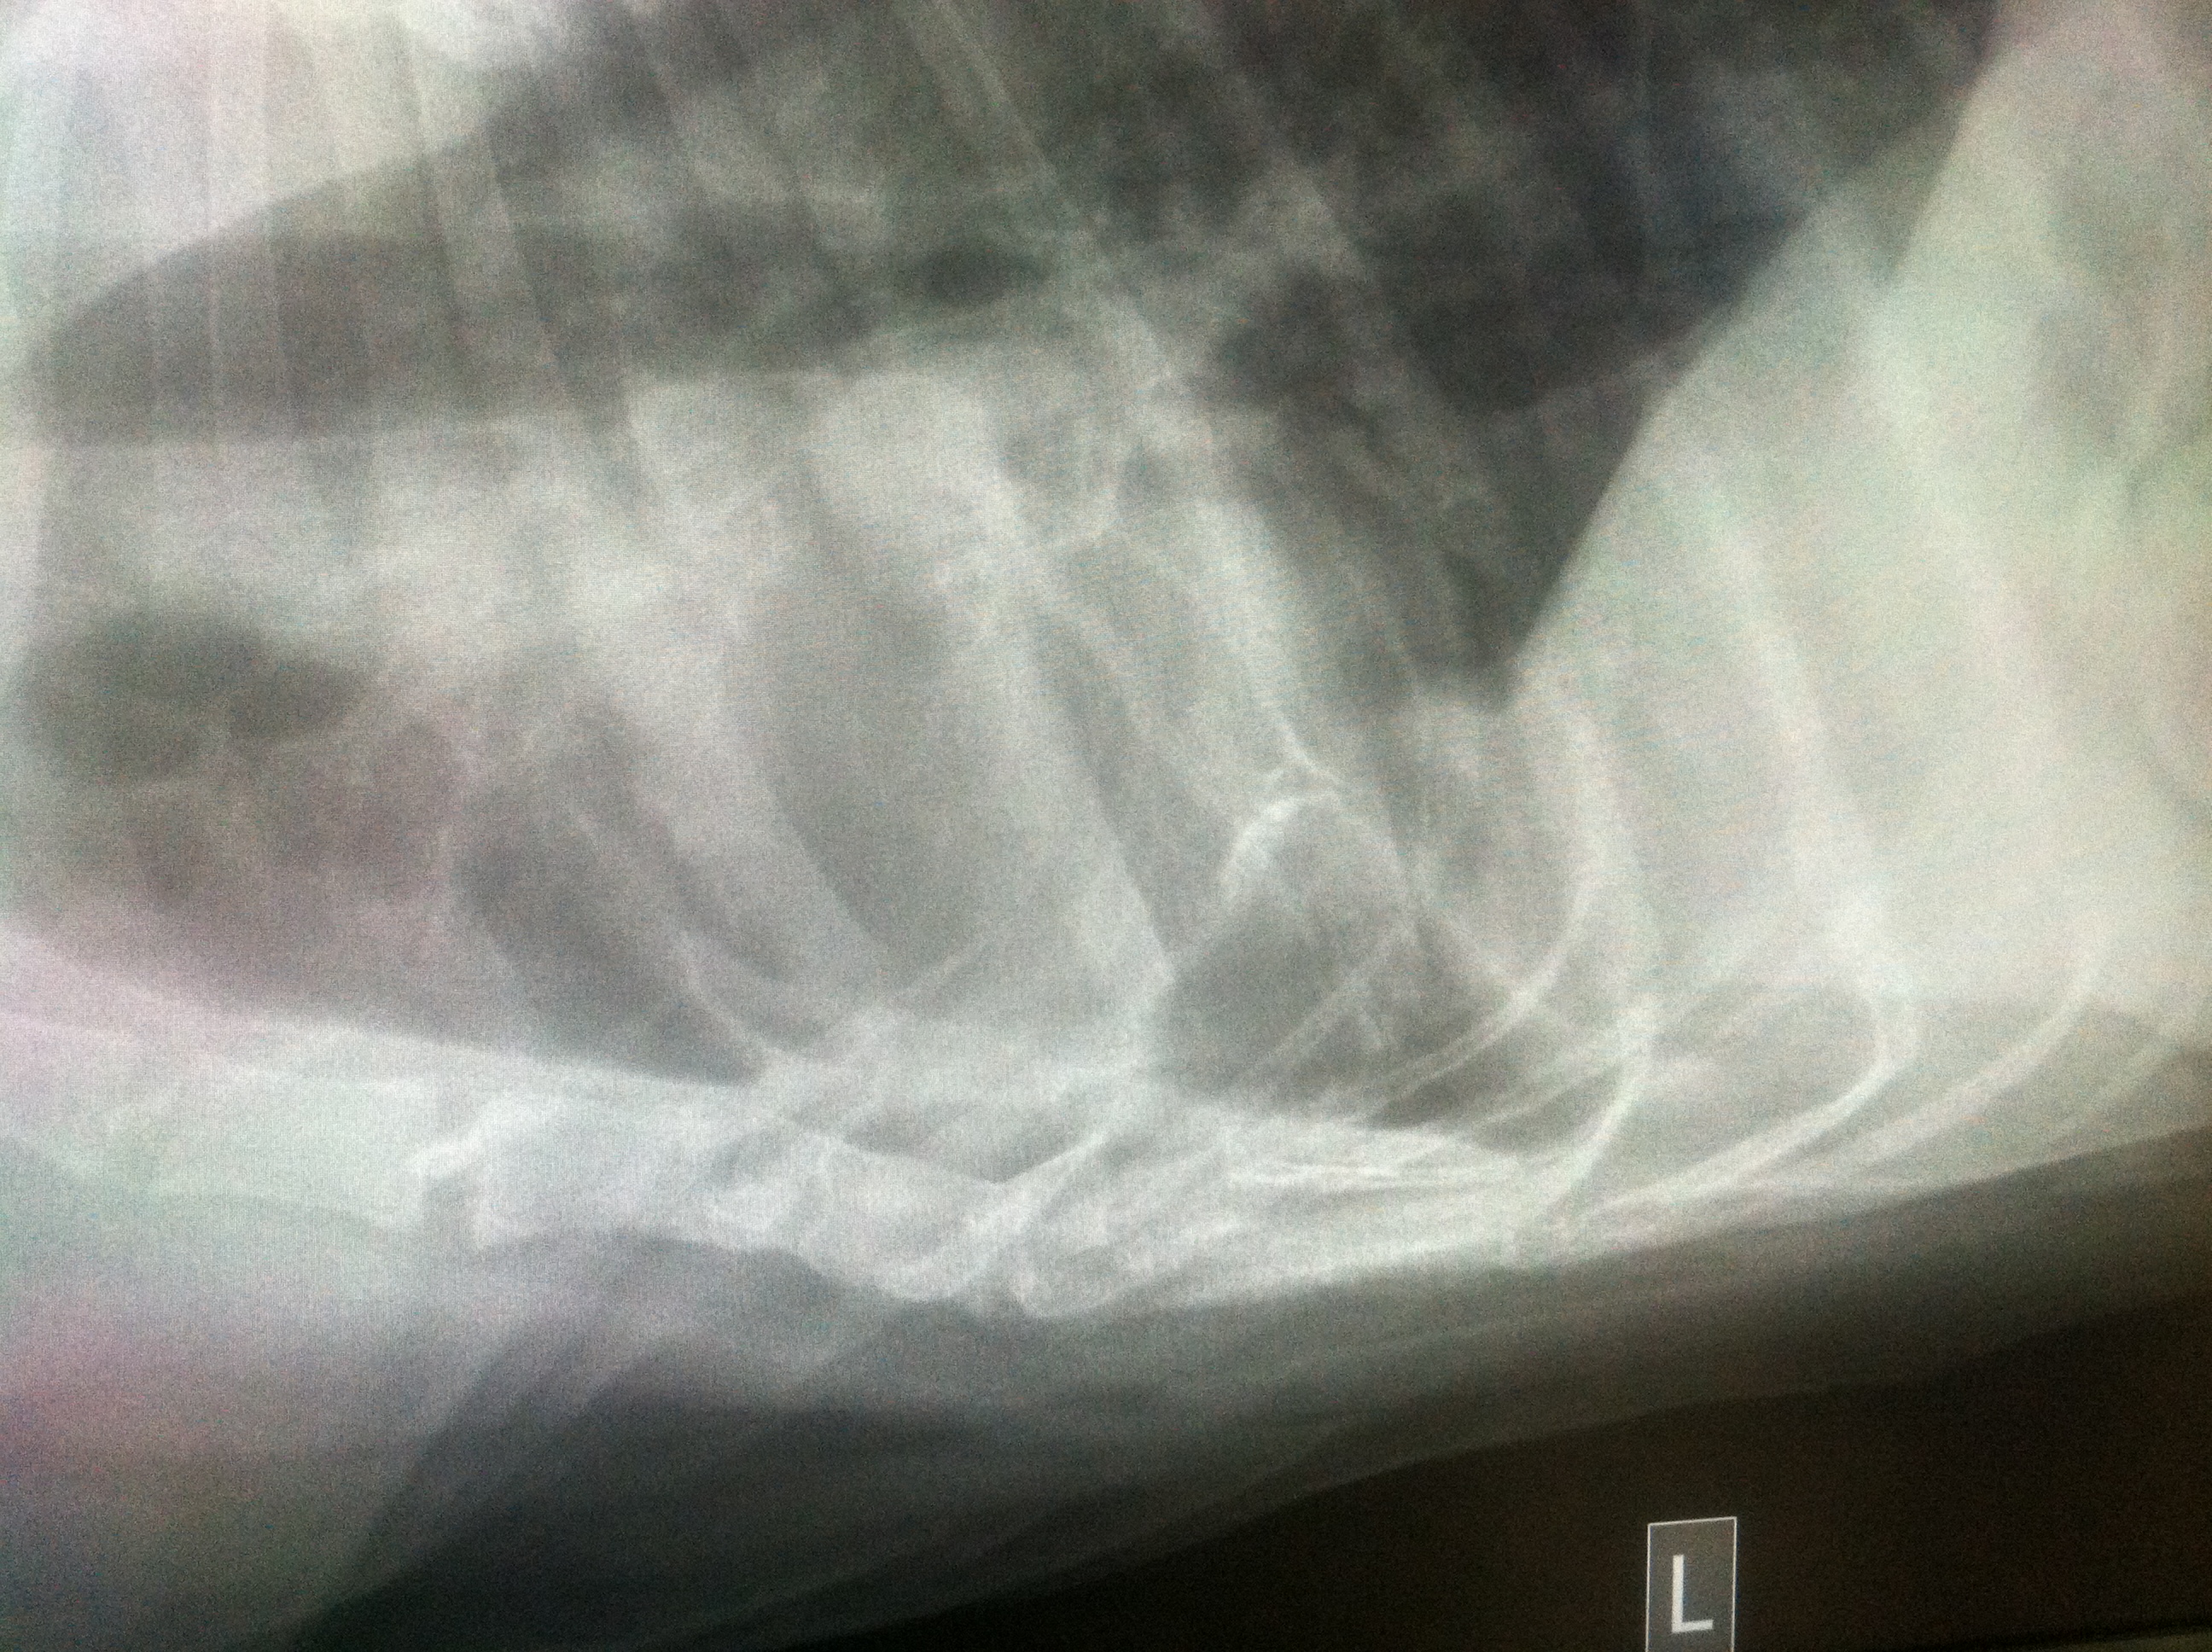

WEEK 3

I am not going to act like I know a lot about what these x-rays are showing because reading x-rays is not my forte, but I can tell you what was explained to me:

Pleural effusions appear on chest X-rays as white space at the base of the lung. Pleural effusion obscures the silhouette of the heart

It’s really hard to see Sherman’s lung in these small pictures but you can see the white space in the top two pictures and his heart has obvious loss of details compared to the 3rd x-ray.

Pnuemothorax means air in the chest cavity.

In the first 2 pictures there is mild pneumothorax in Sherman’s chest cavity.

Again, it’s hard to see in these pictures. Taking x-rays of the chest of a giant breed dog is no easy task. The x-rays plates just aren’t big enough to accommodate them.